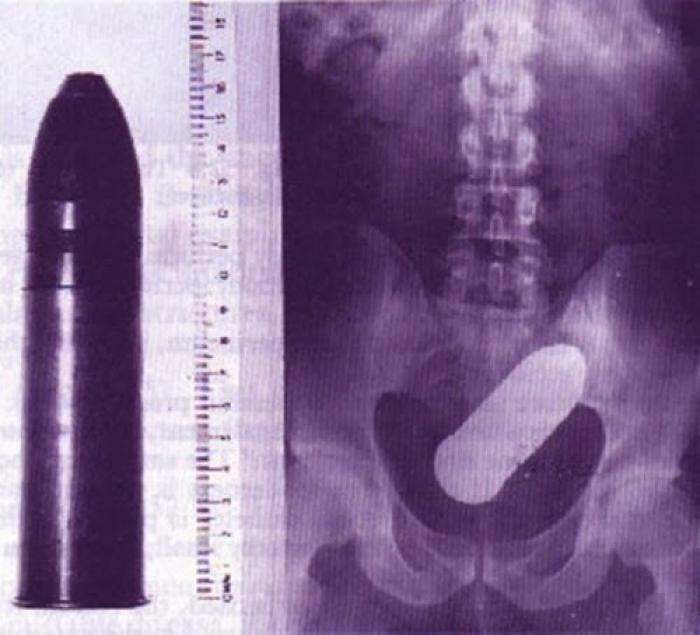

Razele X ne dovedesc că oamenii "pierd" adesea o mulțime de lucruri în propriul corp.